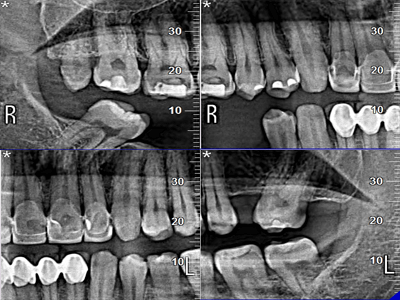

Pro Patient: Our state-of-the-art cone-beam computed tomography (CBCT) technology could selectively image the sinus, oral maxillofacial, para-nasal sinuses, ear & throat regions.

We practice the ALARA principle; (As low as Reasonably Achievable) all scans are restricted to the “Field of View” of your dentist’s prescription. It is taken using (1) pulsed x-ray exposure protocols, (2) real-time-automatic exposure control of the x-ray dose based on the patient’s actual bone density & (3) high resolution digital x-ray image sensors. These factors lead to a significant reduction in x-ray exposure equivalent to only 10% of the x-ray dose of a medical CT-Scan.

The aforementioned technology is inherent in the “myRay X9 CBCT Scan” that we use. myRay X9 is an Italian-made Oral Maxillofacial CT-Scan, certified compliant by European, Japan, USA and other international authorities in radiation safety.

Proactive Dental Management thru our 3D Imaging Manipulation Software

With Oral Maxillofacial CT Scans, your dentist enhances his ability to proactively manage your health concern thru accurate diagnosis & better treatment planning. Moreover, the patient benefits from a painless,low radiation dose CT Scan procedure.